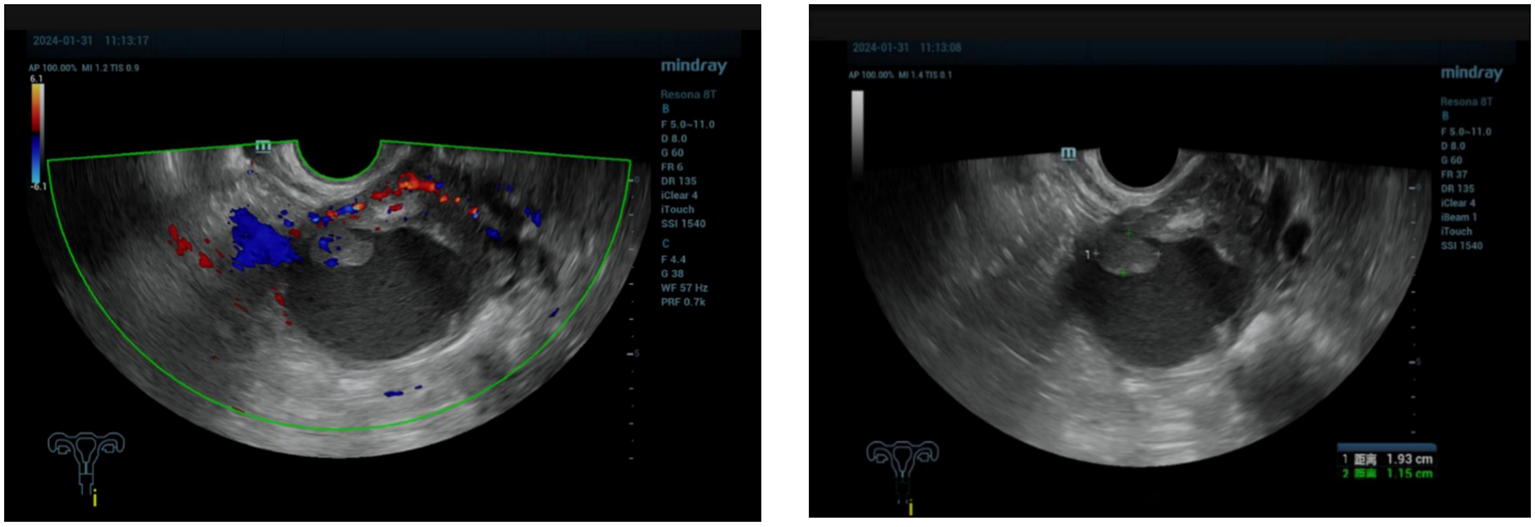

A 71-year-old postmenopausal woman presented with scant dark-red vaginal bleeding. She sought medical treatment at Qingdao University Affiliated Hospital. B-ultrasound revealed an enhanced echo in the lower uterine segment, measuring approximately 5.6×4.8×3.8 cm, raising suspicion of endometrial carcinoma (Figure 1). Diagnostic endometrial biopsy subsequently confirmed adenocarcinoma, favoring endometrioid subtype. Serum tumor markers were as follows: Alpha-fetoprotein (AFP) 15.480 ng/mL (reference range: 0–7 ng/mL), carcinoembryonic antigen (CEA) 8.070 ng/mL (reference range: 0–5 ng/mL), carbohydrate antigen 199 (CA199) 98.280 U/mL (reference range: 0–30 U/mL), and carbohydrate antigen 125 (CA125) 8.080 U/mL (reference range: 0–25 U/mL). Whole-body PET/CT demonstrated an ill-defined hypermetabolic soft-tissue nodule (SUVmax ≈13.8) in the uterine corpus-cervix junction and an intracavitary protruding nodule (SUVmax ≈9.3) in the fundus, with no enlarged lymph nodes in the bilateral iliac/inguinal regions, consistent with uterine malignancy (Figure 2). Following an initial diagnosis of endometrial malignancy, the patient was admitted to our gynecology department on February 16, 2024, for surgery. Following admission, a comprehensive medical history was documented. The patient is G3P2A1. Fourteen years ago, she underwent surgical treatment for rectal cancer, followed by adjuvant chemoradiotherapy. Regular postoperative surveillance revealed no signs of recurrence. On February 20, 2024, the patient underwent laparoscopic exploration Laparoscopy revealed dense adhesions between the rectum/sigmoid colon and left pelvic wall, with fibrosis impeding vascular dissection. Frozen section pathology indicated moderately-to-poorly differentiated adenocarcinoma with necrosis and calcification, infiltrating nearly the full myometrial thickness. Consequently, we performed laparoscopic extrafascial total hysterectomy, bilateral adnexectomy, right pelvic lymph node dissection, para-aortic lymph node biopsy, and pelvic adhesion lysis.

Figure 1. The ultrasound showed enhanced echo in the lower segment of the uterus, ranging from 5.6×4.8×3.8cm, considering endometrial malignancy.

Figure 2. PET-CT showed nodules of soft tissue density at the base of the uterine body, protruding intrauterine, with increased metabolism, which was consistent with malignant uterine tumors.